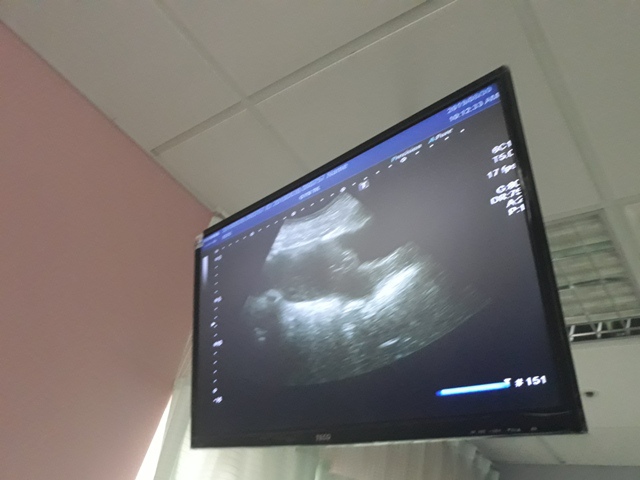

當小純進入診間看診時,我並沒有進去,因為小純說,有時男生不能進去,會被請出來。在外頭等待的我感到很緊張,不久之後,謢理人員請我進入診間,我嚇了一跳,想說發生什麼事了,進入之後,得知小純真的懷孕了,而且已懷了九星期又五天。看診的醫師說,驗孕棒第二條線淡淡的,沒想到胚胎照出來那麼大了,說Baby很健康。還說一閃一閃的是他的心跳,有頭、有手、有腳還有臍帶。小純後來說看了內心覺得很感動,才叫我一起進去看。

小純肚子裡的Baby超音波圖↓